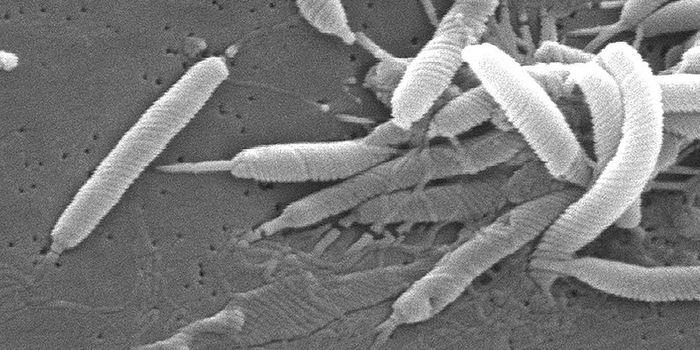

MAR 16, 2015MicrobiologyTargeting deadly, drug-resistant bacteria poses a serious challenge to researchers looking for antibiotics that can kill ...